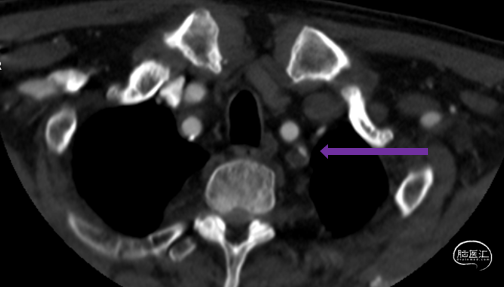

头颈CTA:左侧椎动脉起始、左侧锁骨下动脉重度狭窄。

LSub

LV1